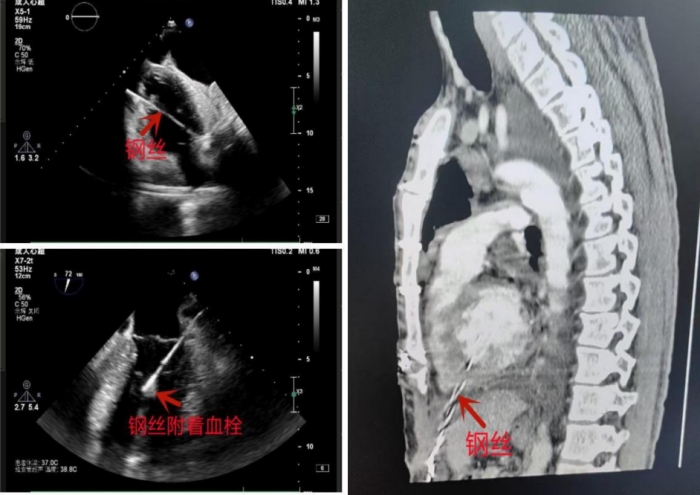

42岁的长沙男子蒋舟(化名)在家不慎发生意外。一根细长的钢丝刺破他左侧肋下皮肤,并以一个刁钻的角度直接扎进了心脏。这根钢丝从右心室心尖部刺入,穿透分隔左右心室的室间隔进入左心室,继而穿透左心室与左心房之间的“门”——二尖瓣,进入左心房,并在左心室内引发了血栓形成。

其一是致命出血风险。由于心脏时刻处于跳动状态,钢丝可能随着心跳活动而发生移位。一旦它穿透相对薄弱的左心房壁,就会引发难以遏制的大出血,后果极为严重。其二是血栓栓塞风险。钢丝作为异物,会持续刺激心脏内流经它的血液,极易诱发血栓形成。目前,患者左心室内已出现了血栓。这些血栓一旦脱落,若进入体循环,可能堵塞脑部血管,引发脑栓塞;也可能堵塞肢体血管,导致肢体坏死;若右心室内出现血栓形成进入肺循环,则可能堵塞肺动脉,引发肺栓塞,造成呼吸循环衰竭,严重威胁生命。

手术过程困难重重且充满挑战,关键要点在于:一是克服“二次开胸”困难,患者三年前做过心脏手术,心脏与心包已形成广泛粘连,心脏解剖游离困难,再次开胸风险极大;二是启用“体外循环”,手术团队使用该技术暂时替代患者心肺功能,让心脏停跳;三是精细“拆弹”。在心脏停跳状态下,医生成功取出贯穿心脏的12厘米长的钢丝,彻底清除左心室内形成的血栓、左侧胸腔内的积血,并修复被钢丝穿透损伤的二尖瓣,最终成功“排雷”,将患者从死亡边缘救了回来 。